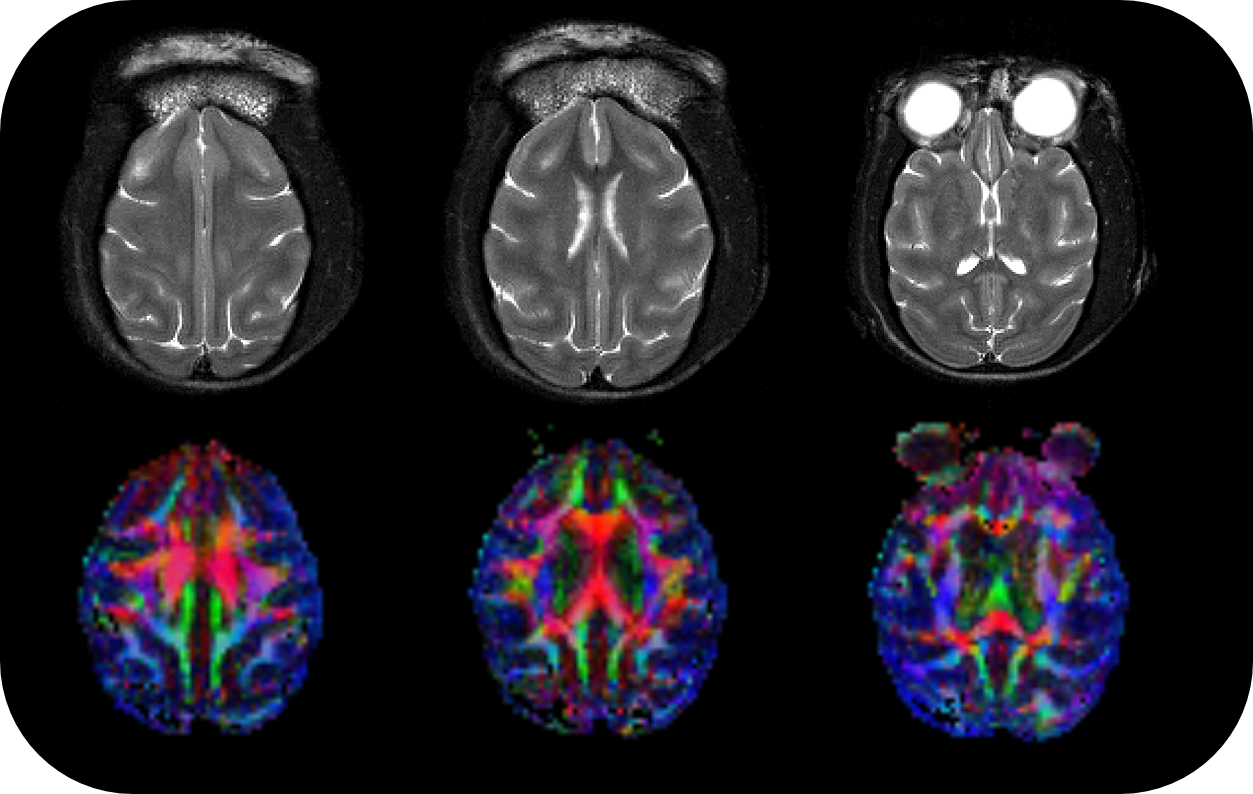

• Complete RF coil portfolio for mice and rats available, including coils for head, brain, cardiac, body, optogenetics, Arterial Spin Labeling, multi-channel array coils with up to 16 channels, and x-nuclei

• MRI CryoProbes with 2 element, 4 element, or as 13C for mice as well as 4 element for rat delivering an exceptional increase in sensitivity

• MRI sequence portfolio of more than 1,000 sequence variations, including wireless cardiac imaging using navigator based IntraGate methods with cartesian or radial readout, as well as short echo time imaging, such as UTE and ZTE